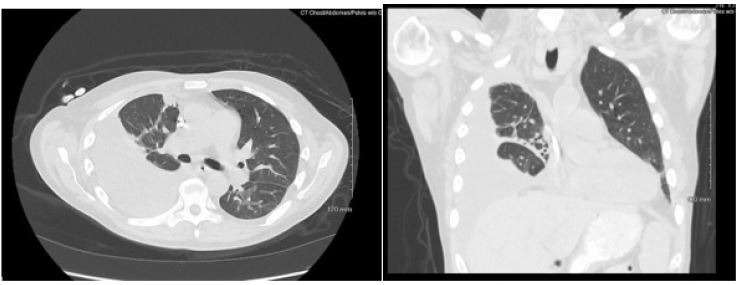

Patient presented with elevated blood pressure at 174/88. BMP was significant for Na 133, K 4.6, BUN 29, Cr 5.3. CMP is significant for Albumin 2.5. CBC was significant for Hb 8.7, Hct 25.0. D-dimer was found elevated at 4,670. PT and INR were normal. ABG significant for pH 7.52, pCO2 31.4, HCO3 25.3. A chest x-ray on admission demonstrated a large right-sided pleural effusion, contributing to significant compressive atelectasis of the right lung and leftward deviation of the mediastinal structures. Thoracentesis was performed, which demonstrated blood- tinged serosanguinous fluid. Transthoracic echocardiogram demonstrated EF 60-65%, LV diastolic dysfunction, with trace mitral and tricuspid regurgitation, and was negative for pericardial effusion. CT Chest demonstrated a large volume right-sided pleural effusion without pneumothorax, with extensive progressive atelectasis throughout the right lung. There was also a trace left-sided pleural effusion and pleural thickening with round atelectasis in the posterior left lower lobe, as well as minimal interstitial edema in the left lung. A chest tube was placed with consistent drainage throughout admission. Repeat chest x-rays continued to demonstrate pleural effusion. Thoracotomy, decortication, and pleurodesis were performed with Video-Assisted Thoracoscopic Surgery (VATS), with significant improvement of symptoms. The pleural fluid biopsy was negative for malignancy and revealed fibrocollagenous tissue with chronic inflammation and a few reactive epithelial cells. Thorough review of the patient’s medication list led to suspicion that the patient’s 50 mg Hydralazine three times a day may be the offending agent. Anti-histone antibody titers were found to be elevated at 3.7. Free Kappa and Lambda light chains were elevated. Antinuclear Antibody (ANA) titers were found to be negative. Hydralazine was discontinued, and after chest tube removal and improved chest x-ray, the patient was discharged home. It was recommended that the patient follow up with their primary care provider and rheumatologist.

Figure 2: Axial and coronal view of chest CT with IV contrast demonstrating large right sided pleural effusion with compressive atelectasis.

Images are Not Display Check it